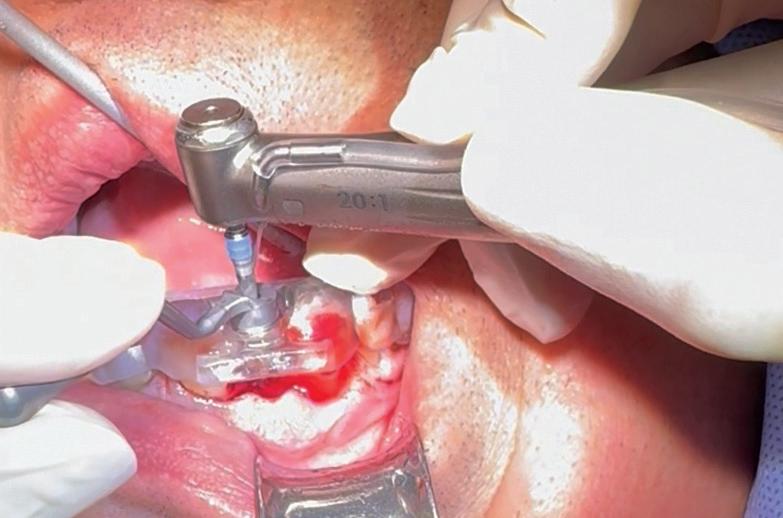

Traditional dental implants use a titanium post that fuses directly to the jawbone to support a ceramic crown, and the surgery often cuts or damages nearby nerves. To tie these inert pieces of metal into the body’s sensory system, the Tufts team developed an implant wrapped in an innovative biodegradable coating. This coating contains stem cells and a special protein that helps them multiply and turn into nerve tissue. As the coating dissolves during the healing process, it releases the stem cells and protein, fueling the growth of new nerve tissue around the implant.

The coating also contains tiny, rubbery particles that act like memory foam. Compressed so that the implant is smaller than the missing tooth when it’s first inserted, these nanofibers gently expand once in place until the implant snugly fits the socket. This allows for a new minimally invasive procedure that preserves existing nerve endings in the tissue around the implant.